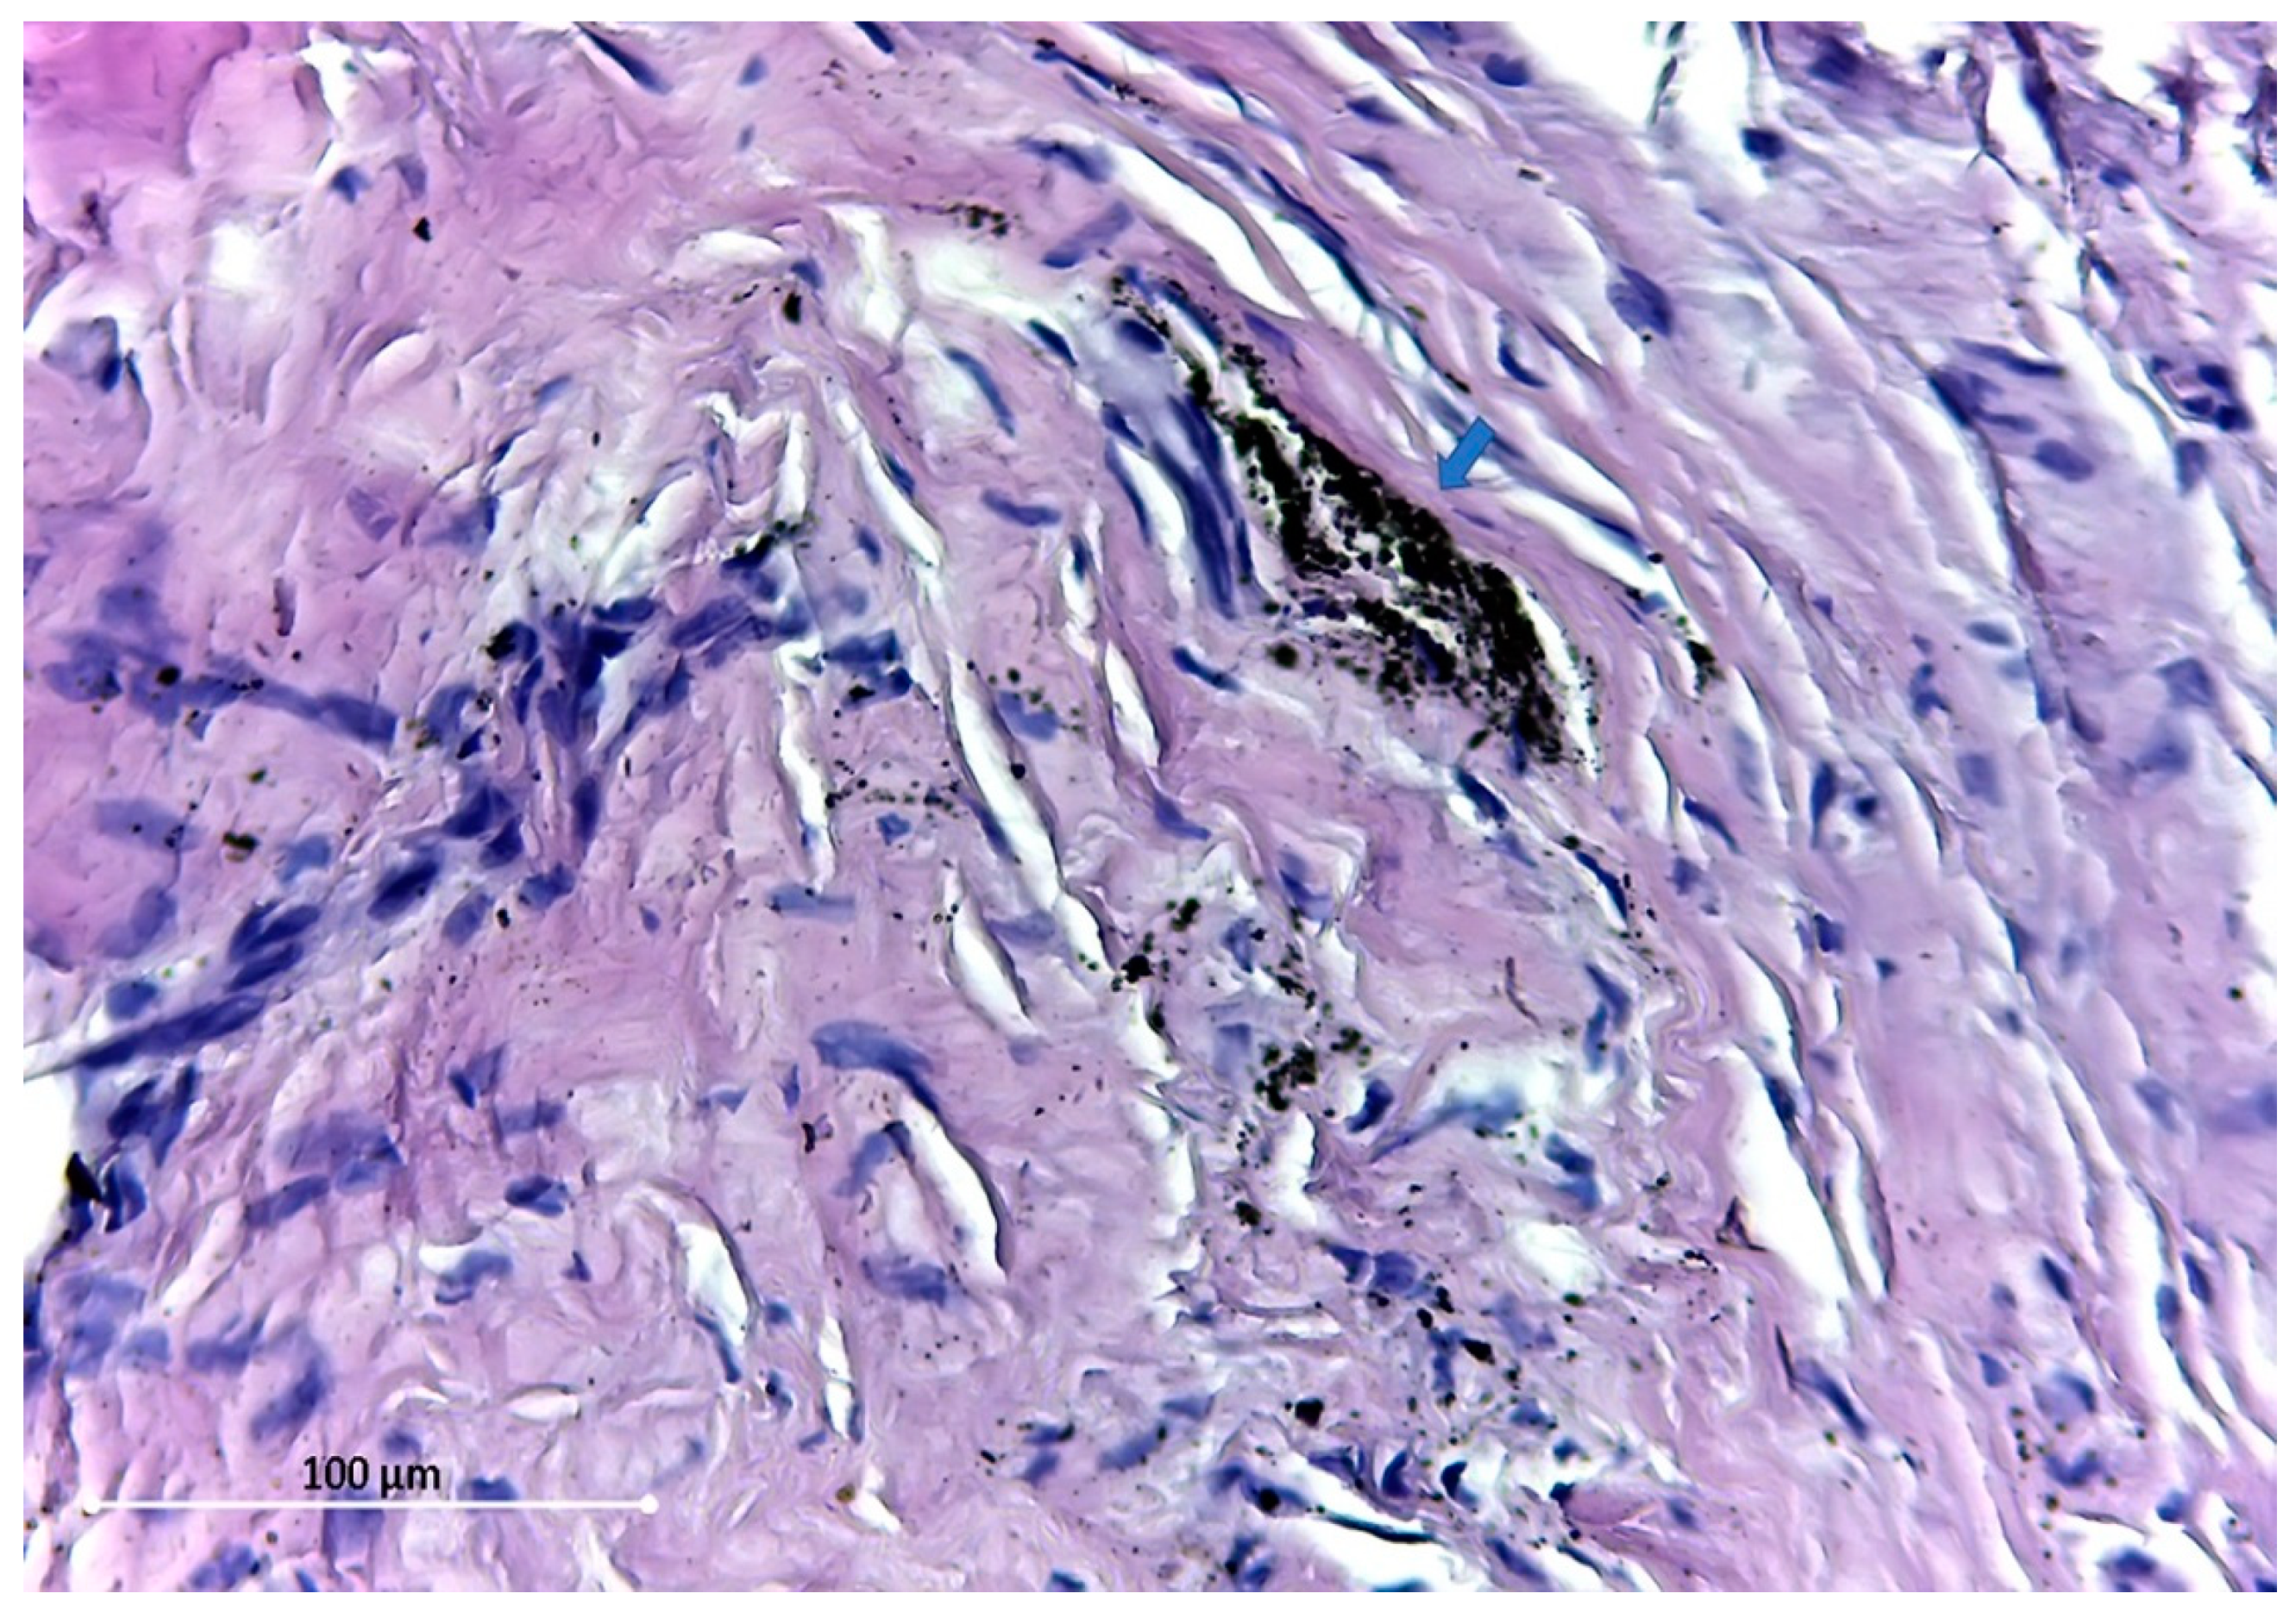

The particles found are of different sizes, varying from 54.5 Micron (Figure 3) to dust-like 1 Micron particles (Figure 4).

The distribution pattern of these tiny dust-like particles suggests the disintegration of larger particles. All the particles found were extracellular.

Figure 3. Large debris (red arrow), near a cluster of small particles (blue arrow). HE stain ×400.

Figure 4. Dust-like (1 micron) particles—blue arrow. HE stain ×400.